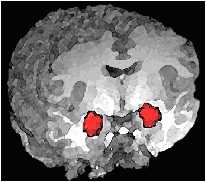

1. Ein

im Laufe ihres Lebens stärker auf- und ausgebautes und zu heftig reagierendes Angst- und Schadensvermeidungssystem,

2. insbesondere eine kleine Gehirnregion, die Mandelkerne (Amygdalae) genannt wird. Die Mandelkerne spielen unter anderem die zentrale Rolle beim Aufbau unserer Reaktionen in stressigen Situationen,

3. zu wenig Serotonin in den Serotonin-Synapsen des Vorderhirns und

4. die kurze Variante des Gens für den Aufbau des Serotonin-Transporter-Eiweißes (5-HTTLPR- oder SerT-Gen).

Im Juli 2002 brachte eine amerikanische Gen-Studie ans Licht, dass bei Menschen, welche die kurz/kurze oder lang/kurze Gen-Variante des SerT-Gens von ihren Eltern geerbt haben, ihr linker Mandelkern aktiver ist, wenn sie Angst verzerrte Gesichter betrachten, als bei Menschen, welche die lang/lange Gen-Variante geerbt haben.

“Die Auswirkungen unterschiedlich langer Gen-Varianten (kurz/kurz, kurz/lang oder lang/lang) auf das Reagieren der Mandelkerne auf Angst auslösende emotionale Reize könnten dazu dienen, einen Teil unserer Wesensart und gefühlsmäßigen Entwicklung zu formen”,

schlossen Ahmad Hariri und Daniel Weinberger vom NIMH, Clinical Brain Disorders

Branch, ihre Studie im Heft Juli/2002 des renommierten Wissenschaftsmagazins :

Quelle: Haririi, Ahmad R. und Holmes, Andrew: Genetics of emotional regulation: The role of the serotonin transporter in neural function, TRENDS in Cognitive Sciences, Heft April 2006, S. 182-193.

Was läuft im Gehirn von Menschen mit Sozialphobie anders ab?

Die Gehirn anatomischen Ursachen der Sozialphobie sind Über-Reaktionen von

Nervenzellen der Amygdala und gleichzeitig Unter-Reaktionen von Nervenzellen im

Vorderhirn. Wenn ein sozialphobischer Mensch über etwas für ihn wahrscheinlich

Furcht auslösendes nachdenkt – meinetwegen über

eine kritische Bemerkung, seine Teilnahme an einer Party oder einem Betriebsausflug -, “feuert” seine Amygdala Angstsignale, woraufhin sein Vorderhirn denkt:

“Ich sollte nicht nervös sein. Das sind

doch auch nur ganz normale Leute wie ich. Wo soll denn da überhaupt das Problem sein?” Aber, weil seine Amygdala überaktiv und sein Vorderhirn unteraktiv Signale

“feuern”, gewinnt immer die Amygdala. Menschen mit einer Sozialen Angststörung erhalten mehr Signale von der Amygdala und weniger Rückmeldungen vom Vorderhirn, so dass sie ohne

therapeutische oder fachärztliche Hilfe die

stärkeren Angstsignale ihrer Amygdala nicht in den Griff bekommen können:

Blair, K. et. al., American Journal of Psychiatry, 2008, Sept. 165(9), S.1193-1202.

Linke Amygdala (links) und mittleres Vorderhirn (rechts)

Copyright 2010 by Neuropsychopharmacology, Lisa Shin